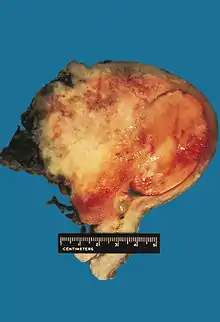

In gross appearance, MMMTs are fleshier than adenocarcinomas, may be bulky and polypoid, and sometimes protrude through the cervical os. On histology, the tumors consist of adenocarcinoma (endometrioid, serous or clear cell) mixed with the malignant mesenchymal (sarcoma) elements; alternatively, the tumor may contain two distinct and separate epithelial and mesenchymal components. Sarcomatous components may also mimic extrauterine tissues (e.g., striated muscle, cartilage, adipose tissue, and bone). Metastases usually contain only epithelial components.